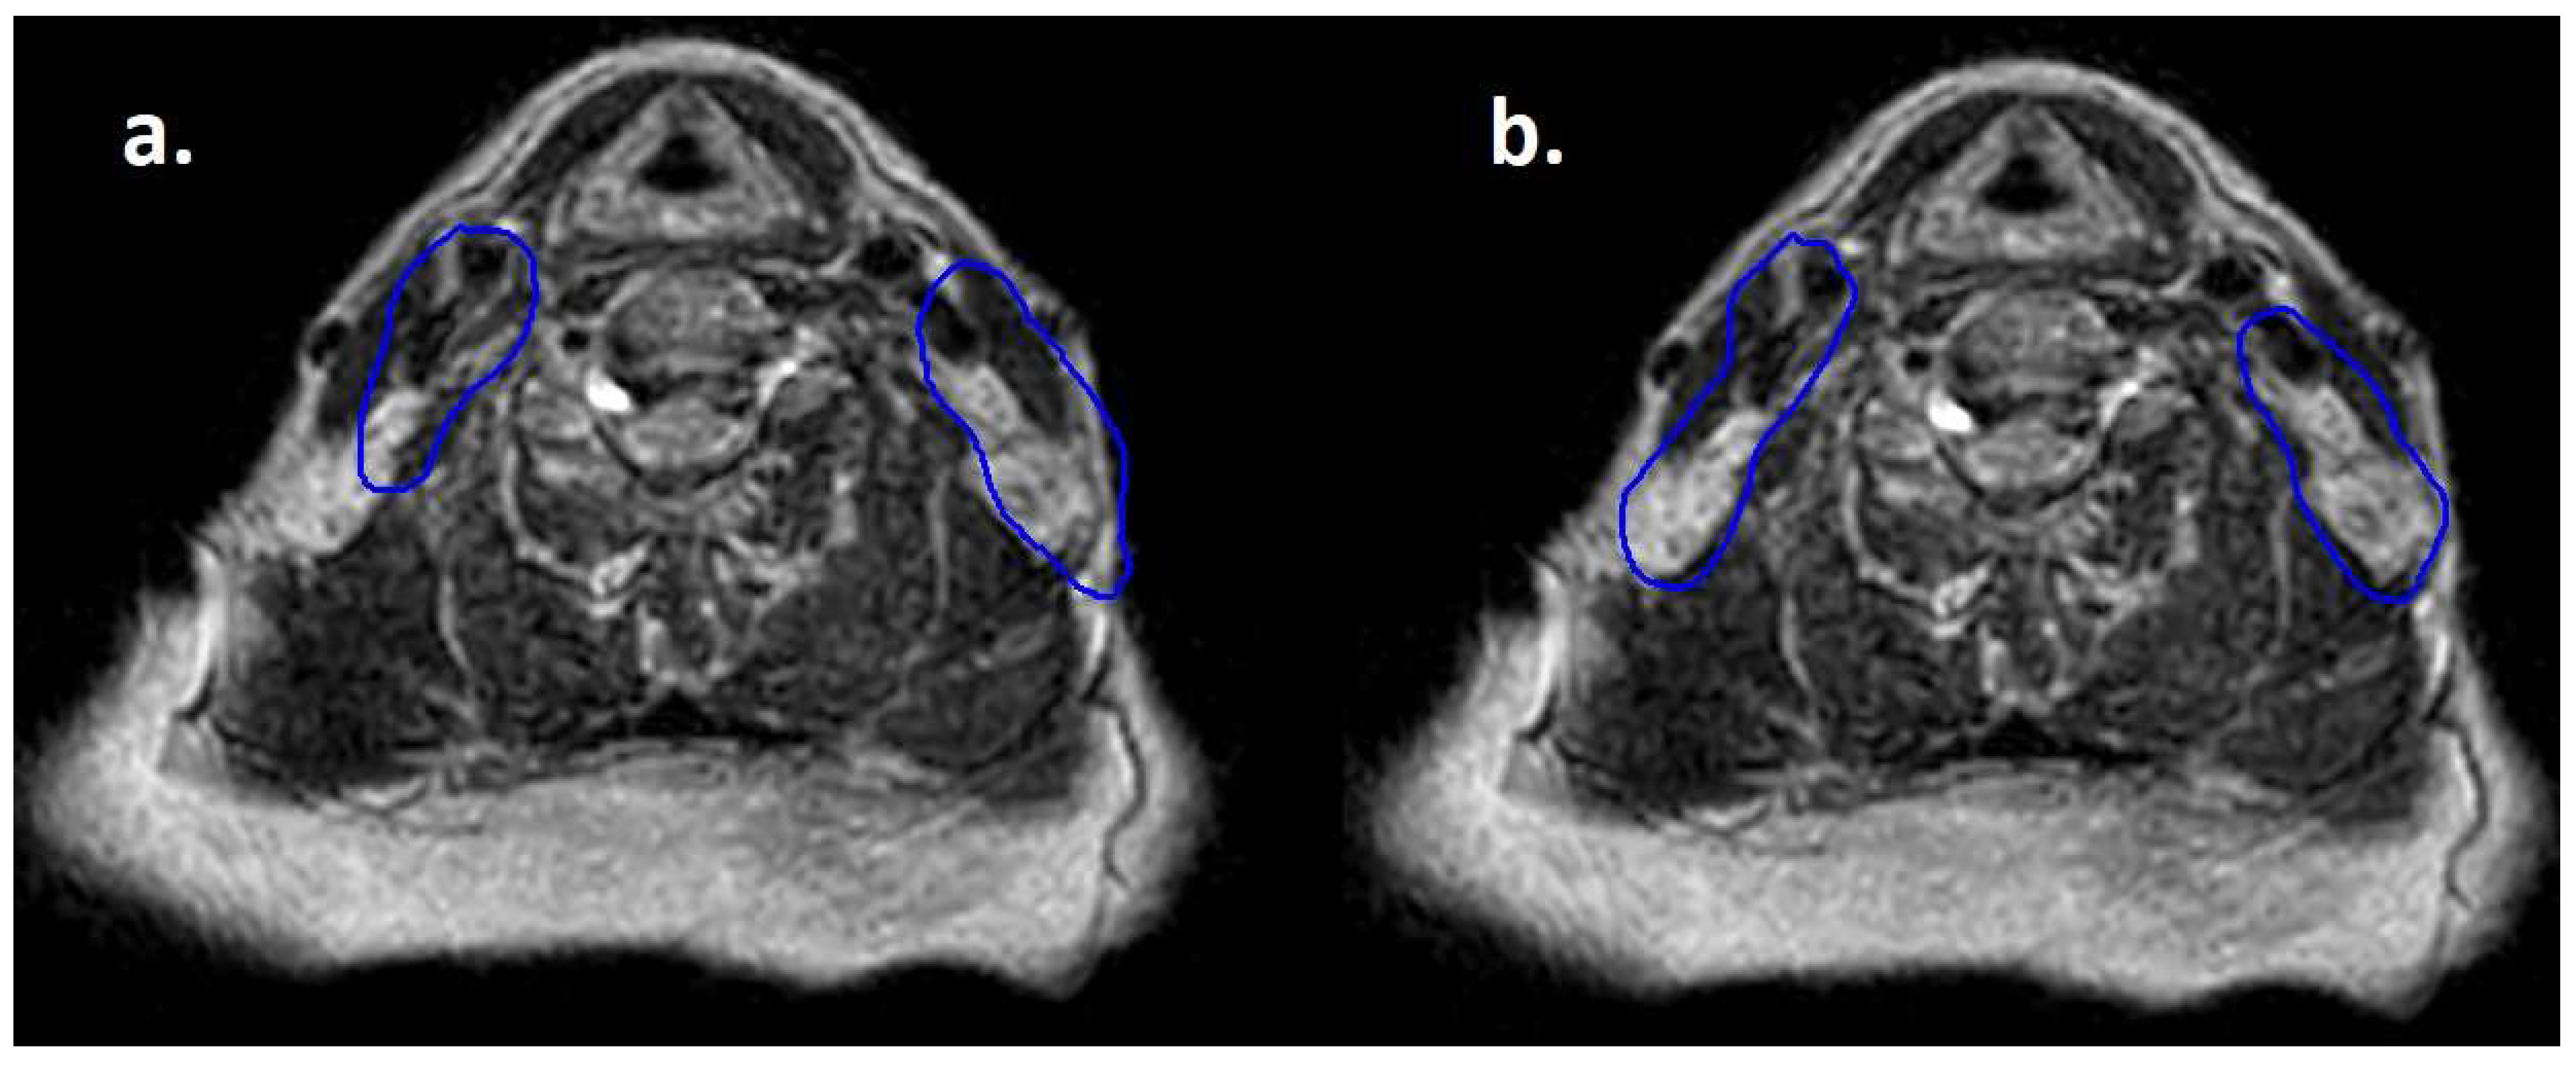

Moreover, lymphomas are radiosensitive neoplasms that tend to respond early during the course of radiotherapy, often leading to a substantial volume reduction (as exemplified in Figure 1). While “conventional” CT-based image-guided radiotherapy (IGRT) might allow for the detection of major volumetric variations, MRI-based IGRT enables the identification of even slight differences due to improved soft tissue contrast. Moreover, in our cohort every patient was treated using a daily adapt-to-shape workflow, in which contours of the target volumes and OARs are manually edited for each fraction on the basis of daily MR imaging (as exemplified in Figure 2) and the treatment plan is extensively recalculated. The possibility to adapt contours and the treatment plan on the basis of daily MRI scans could improve dose distribution and guarantee optimal target coverage compared with conventional RT, while sparing surrounding organs at risk [21,22]. This should conceptually result in reduced treatment-related toxicity; nonetheless, clinical data to confirm this hypothesis are awaited (also due to the novelty of this technology).

Figure 2.

Daily MRI at the sixth fraction of radiotherapy of the patient that received bridging therapy before CAR-T with a dose of 3 Gy per fraction. In (a) contours rigidly propagated from simulation MRI; in (b) contours deformably registered, manually edited and used for treatment delivery.